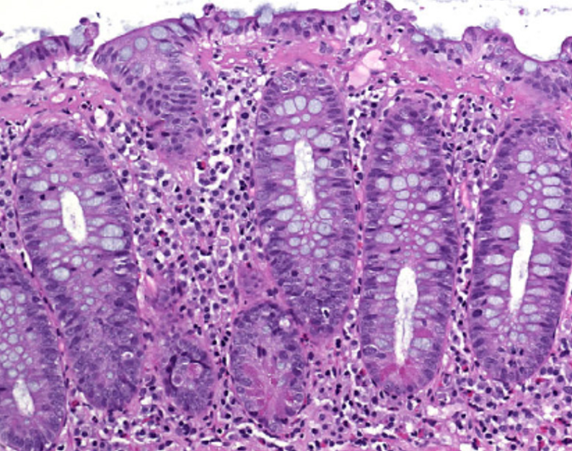

Rektum, sigmoideum, descendens, transversum och sista delen av ascendens är makroskopiskt normala. I första delen av ascendens och cekum är slemhinnan kraftigt inflammerad och har ett närmast gatstensliknande mönster. Slemhinnan i sista delen av ileum (bilden) är rodnad, svullen och lättblödande med talrika petekier. Det finns dessutom ett fibrinbelagt sår, ca 0.5 x 1.5 cm. Efter cirka 10 centimeter in i ileum är slemhinnan normal

Vad tyder denna makroskopiska bild på?

- Morbus Crohn i och med geografi och gatstensliknande mönster

Bedöm biopsin

- Kolonslemhinna med kroniskt och akut inflammatoriskt infiltrat i lamina propria och intraepitelialt. Granulom påvisas. Kryptarkitekturen är oregelbunden.

- Morbus Crohn – granulom ganska specifikt